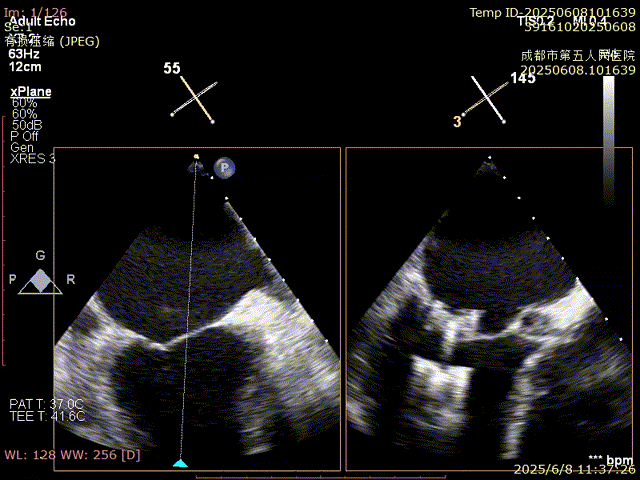

確認夾合位置及效果

即刻反流得到明顯改善